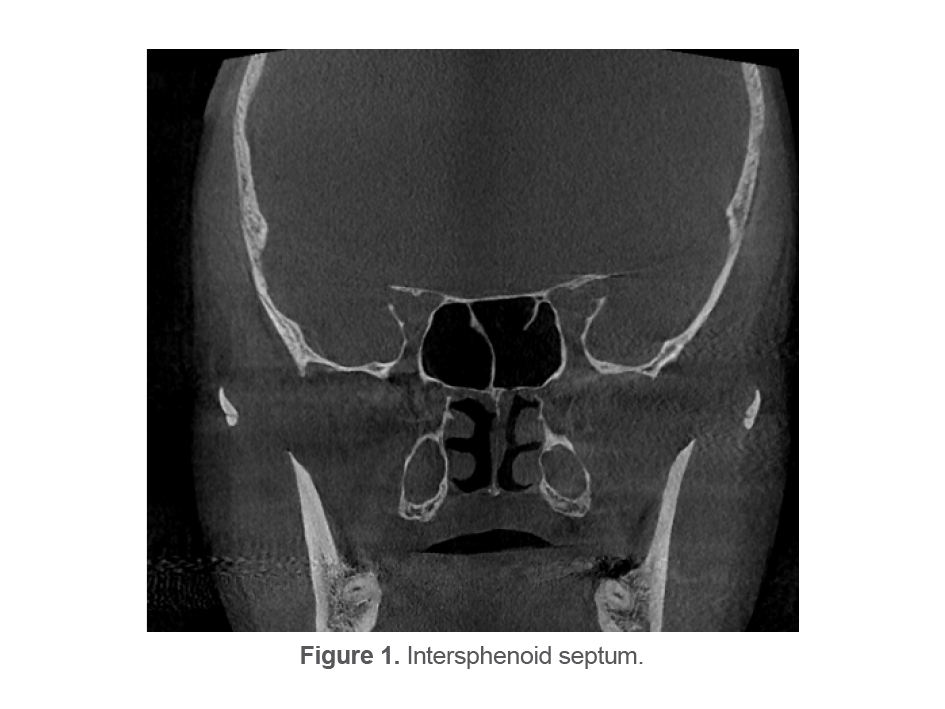

Intersphenoid septa: Presence/absence of inter-sphenoid septa was evaluated on coronal sections. Intersphenoid septum was defined as a skeletal septum that divides the sphenoid sinus into at least two separate cavities (Figure 1).

Intersphenoid septa was absent in 2 cases (1.32%, one male and one female), resulting in formation of one sinus cavity.

The present results revealed that the prevalence of intersphenoid septa was 98.68%. This rate was 99.2% in a study by Movahhedian et al (4), 96.6% in a study by Özer et al (7), and 89.2% in a study by Hamid et al (12).

Figure 1. Intersphenoid septum.